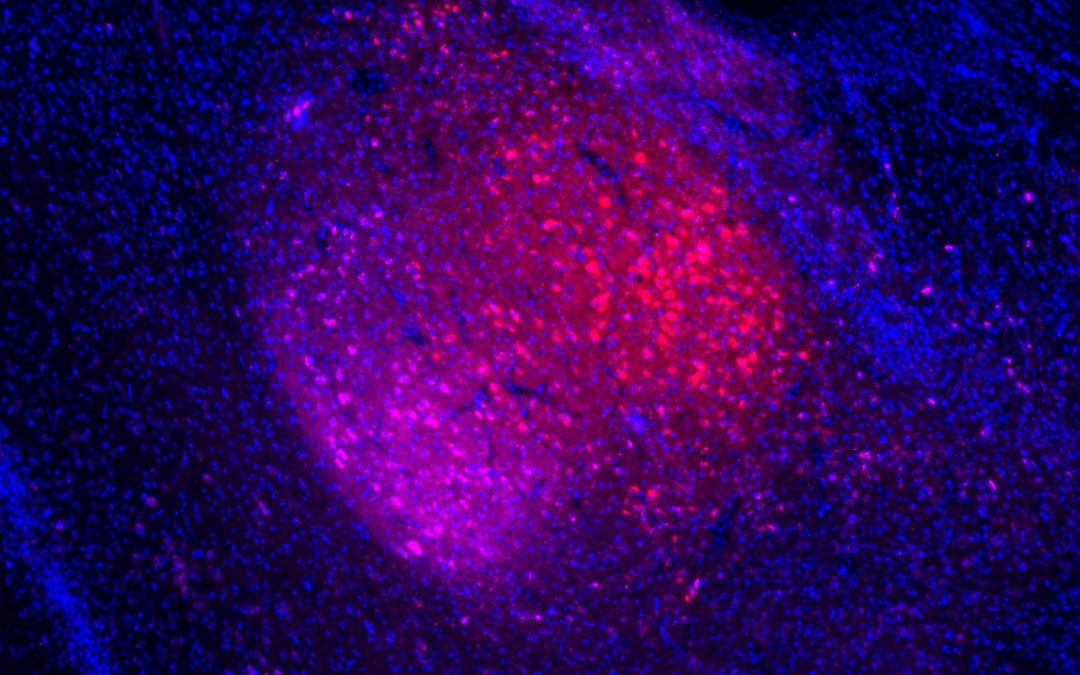

En cas d’insuffisance rénale, la transplantation est le traitement de choix. Toutefois, le risque de rejet demeure important. Une meilleure compréhension de la réponse immunitaire lors du rejet de greffe rénale – et notamment du phénomène d’inflammation...